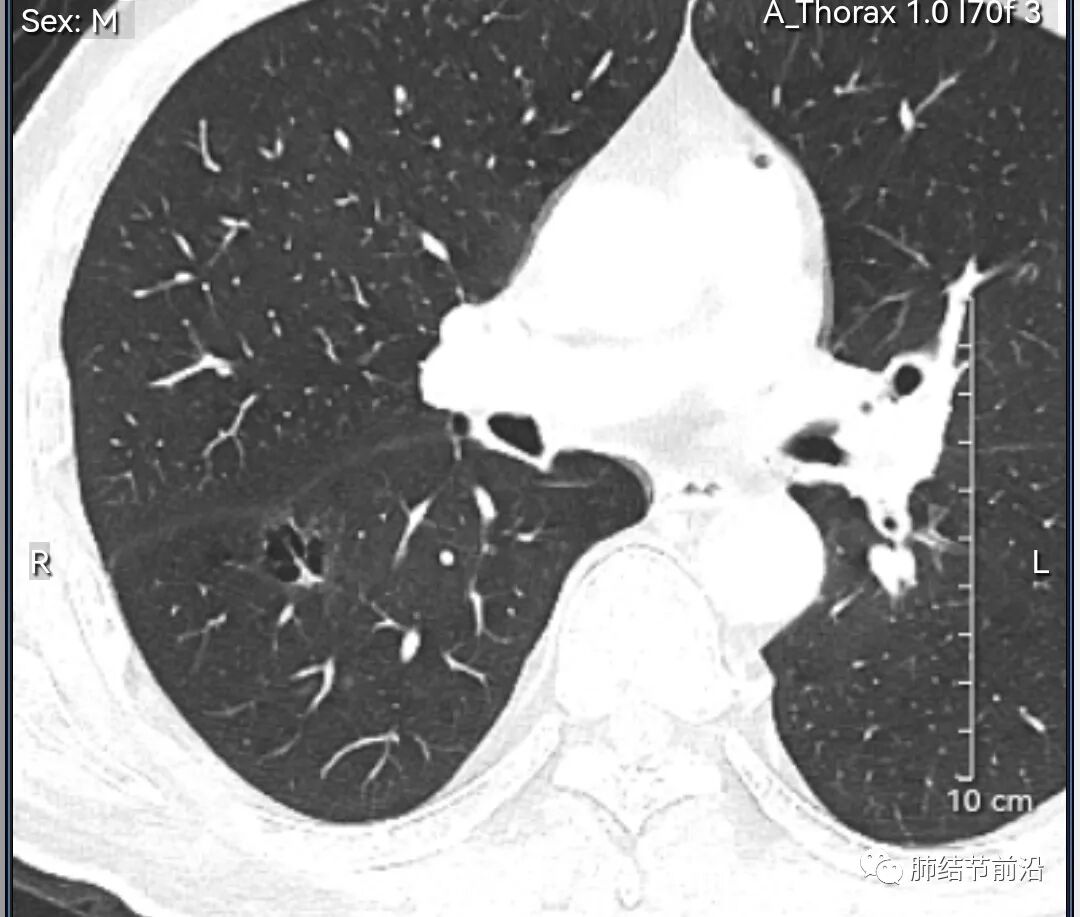

男性,67岁,重度吸烟史。CT发现右下肺囊腔。来看一下这个CT的特点:

该囊腔形态非常有特点,和常见的圆形肺大泡有很大的区别。

1.囊腔中央实性成分,周围有磨玻璃影。

2.囊腔中央有血管。

3.囊腔外周有分叶形态。

4.囊腔有胸膜牵拉。

出现这几种形态,CT可以确认恶性的腺癌。这个囊腔形成的机制,为肿瘤实性成分堵塞细支气管形成活瓣,肺泡内压力增高破裂行成,因此肺内血管成分保留。由于肺泡压力增高,而呈分叶状。另外,也有肿瘤的胸膜牵拉这一特点。

囊腔周围磨玻璃+囊腔中央血管为特征性表现。如果持续存在,几乎可以100%确认为早期肺腺癌。

建议患者手术切除,术后病理为浸润性腺癌,腺泡型,部分为实体型。IA1期,术后不用治疗。